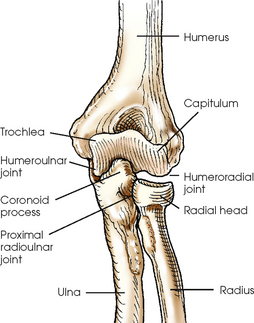

The entire distal end of the humerus is called the humeral condyle and includes two smooth elevations for articulation with the bones of the forearm—the trochlea on the medial side and the capitulum on the lateral side. The medial and lateral epicondyles are superior to the condyle and easily palpated. On the anterior surface superior to the trochlea, a shallow depression called the coronoid fossa receives the coronoid process when the elbow is flexed. The relatively small radial fossa, which receives the radial head when the elbow is flexed, is located lateral to the coronoid fossa and proximal to the capitulum. The olecranon fossa is a deep depression found immediately behind the coronoid fossa on the posterior surface and accommodates the olecranon process when the elbow is extended (Fig. 4-7, C).

The elbow joint proper includes the proximal radioulnar articulation and the articulations between the humerus and the radius and ulna. The three joints are enclosed in a common capsule. The trochlea of the humerus articulates with the ulna at the trochlear notch. The capitulum of the humerus articulates with the flattened head of the radius. The humeroulnar and humeroradial articulations form a synovial hinge joint and allow only flexion and extension movement (Figs. 4-10 and 4-11, A). The proximal humerus and its articulations are described with the shoulder girdle in Chapter 5.